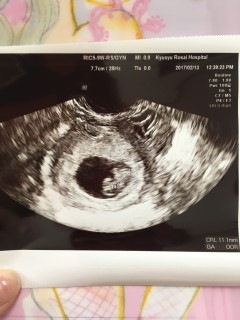

写真:7w5d:桃さん

ちょうど6w0dの頃から続く出血…最初は鮮血で3日ほど経って黒っぽいものに…現在も生理最終日くらいの茶色い出血が続いてて、半ば諦め気味に受診。

大きさも心拍も問題なく成長できてました…(´;ω;`)

CRL11.5mm

4人目になる子なので上(7歳、3歳半、1歳半で全員男の子)の世話で出血してようが身体を気遣うことも出来ず申し訳ないけど…強く育って元気に産まれてきてほしいです!